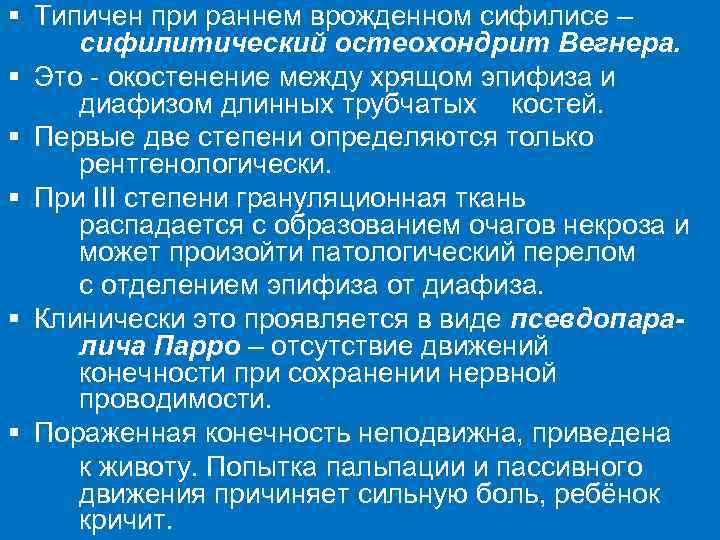

§ Типичен при раннем врожденном сифилисе – сифилитический остеохондрит Вегнера. § Это - окостенение между хрящом эпифиза и диафизом длинных трубчатых костей. § Первые две степени определяются только рентгенологически. § При ІII степени грануляционная ткань распадается с образованием очагов некроза и может произойти патологический перелом с отделением эпифиза от диафиза. § Клинически это проявляется в виде псевдопаралича Парро – отсутствие движений конечности при сохранении нервной проводимости. § Пораженная конечность неподвижна, приведена к животу. Попытка пальпации и пассивного движения причиняет сильную боль, ребёнок кричит.

Рентгенологическое обследование необходимо проводить в первые 3 месяца жизни ребёнка - в более поздние сроки явления остеохондрита могут самопроизвольно разрешиться